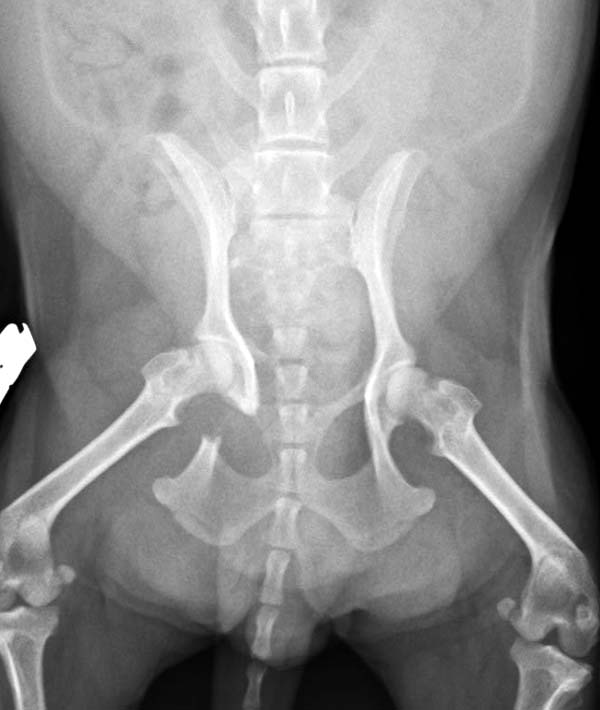

13歳のマルチーズちゃんが骨盤骨折で来院されました。ロッキングプレートを使用した仙腸関節安定化術(TAITAN1.7と1.5)で固定する手術を行いました。術後元気に歩けるようになりました。よかったね。